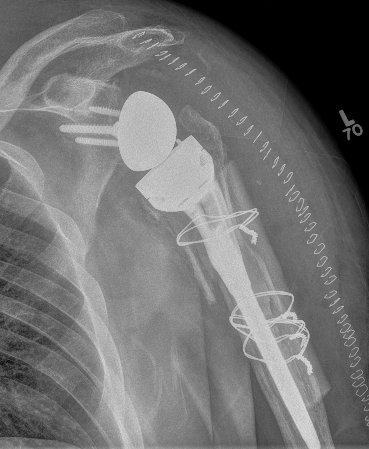

Hum shafthum shaftHum shaft

Stable humeral component treated with ORIF

hum #Hum #Hum #